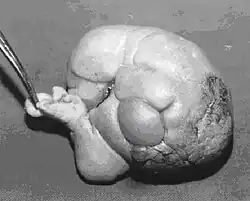

Fetus in fetu

Fetus in fetu (or foetus in foetu) is a rare developmental abnormality in which a mass of tissue resembling a fetus forms inside the body of its twin. An early example of the phenomenon was described in 1808 by George William Young.[1]

There are two hypotheses for the origin of a fetus in fetu. One hypothesis is that the mass begins as a normal fetus but becomes enveloped inside its twin.[2] The other hypothesis is that the mass is a highly developed teratoma. Fetus in fetu is estimated to occur in 1 in 500,000 live births.[3]

A fetus in fetu can be considered alive, but only in the sense that its component tissues have not yet died or been eliminated. Thus, the life of a fetus in fetu is akin to that of a tumor in that its cells remain viable by way of normal metabolic activity. However, without the gestational conditions in utero with the amnion and placenta, a fetus in fetu can develop into, at best, an especially well differentiated teratoma; or, at worst, a high-grade metastatic teratocarcinoma. In terms of physical maturation, its organs have a working blood supply from the host, but all cases of fetus in fetu present critical defects, such as no functional brain, heart, lungs, gastrointestinal tract, or urinary tract. Accordingly, while a fetus in fetu can share select morphological features with a normal fetus, it has no prospect of any life outside of the host twin. Moreover, it poses clear threats to the life of the host twin on whom its own life depends.[4]

Fetus in fetu may be a very highly differentiated form of dermoid cyst, itself a highly differentiated form of mature teratoma.[5]

Fetus in fetu may be a parasitic twin fetus growing within its host twin. Very early in a monozygotic twin pregnancy, in which both fetuses share a common placenta, one fetus wraps around and envelops the other. The enveloped twin becomes a parasite, in that its survival depends on the survival of the host twin, by drawing on the host twin's blood supply. The parasitic twin is anencephalic (without a brain) and lacks some internal organs, and as such is unable to survive on its own.